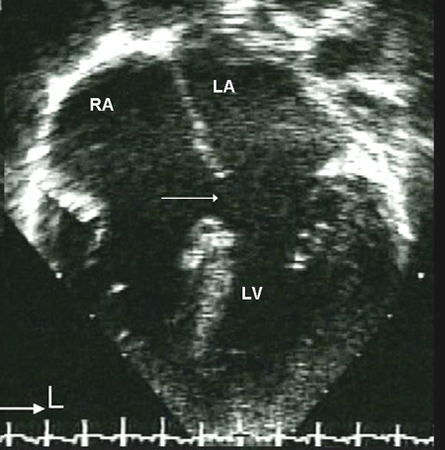

Peri-membranous defects typically occur as a solitary lesion and can sometimes close spontaneously by apposition of the septal leaflet of the tricuspid valve to the defect. Outlet defects may be large and associated with more complex forms of congenital heart disease such as tetralogy of Fallot. Both peri-membranous and outlet VSDs are in close proximity to the right cusp of the aortic valve. Because of the Venturi effect, these defects can cause prolapse of an aortic valve cusp, which results in both a restriction to flow through the VSD and regurgitation of the aortic valve.[22] Inlet defects do not close spontaneously and may be associated with AVSD and AV valve regurgitation. Muscular defects are the most common type of VSDs in newborns and the vast majority close spontaneously before 2 years of age.[Figure caption and citation for the preceding image starts]: Apical 4-chamber echocardiographic image of a muscular VSD (arrow). (RA) right atrium; (LA) left atrium; (RV) right ventricle; (LV) left ventricleImage courtesy of Patrick W. O'Leary, MD [Citation ends].

[Figure caption and citation for the preceding image starts]: Apical 4-chamber echocardiographic image of an ostium primum ASD (arrow). (RA) right atrium; (LA) left atrium; (LV) left ventricleImage courtesy of Patrick W. O'Leary, MD [Citation ends].